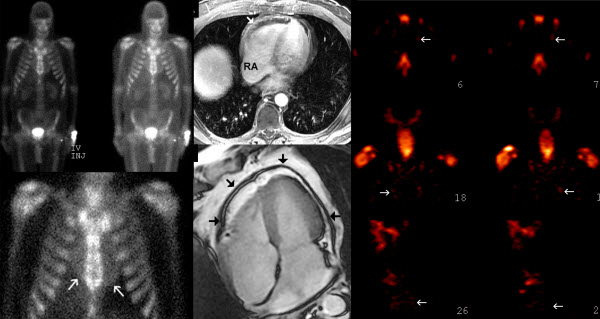

ORLANDO – Si muore sempre meno di infarto, ma si rischiano sempre più gli «effetti collaterali» degli esami cardiologici. Un paziente, che viene oggi ricoverato in ospedale per un attacco di cuore, riceve una quantità di radiazioni, da coronarografie, tomografie o scintigrafie cardiache, pari a 725 Rx del torace.

Una dose di esposizione che è circa un terzo di quella massima consentita, in un anno, a chi lavora in un impianto nucleare. E le conseguenze a lungo termine sono tutte da valutare, ma si sa che le radiazioni ionizzanti possono aumentare le probabilità di sviluppare un tumore. A porre l’accento sui rischi da test è uno studio appena presentato al meeting annuale dell’American Heart Association in corso a Orlando. Spesso i medici prestano attenzione alla dose di radiazioni di un singolo esame, ma non fanno il conto della quantità cumulativa: gli esperti americani della Duke University di Durham lo hanno fatto, analizzando i dati di oltre 60 mila pazienti, e sono arrivati alla conclusione che in media a ogni paziente vengono prescritti 7 esami, durante il ricovero in ospedale per un attacco acuto di cuore, e che la dose di radiazioni accumulata si aggira attorno ai 14,5 millisieverts (il sievert misura il danno provocato da una radiazione su un organismo). «Fra 1980 e il 2006 il numero di test medici che prevedono l’impiego di radiazioni ionizzanti – ha commentato Prashant Kaul, che ha coordinato la ricerca – è aumentato del 700 per cento e un terzo di questi viene praticato a pazienti che soffrono di problemi cardiovascolari».